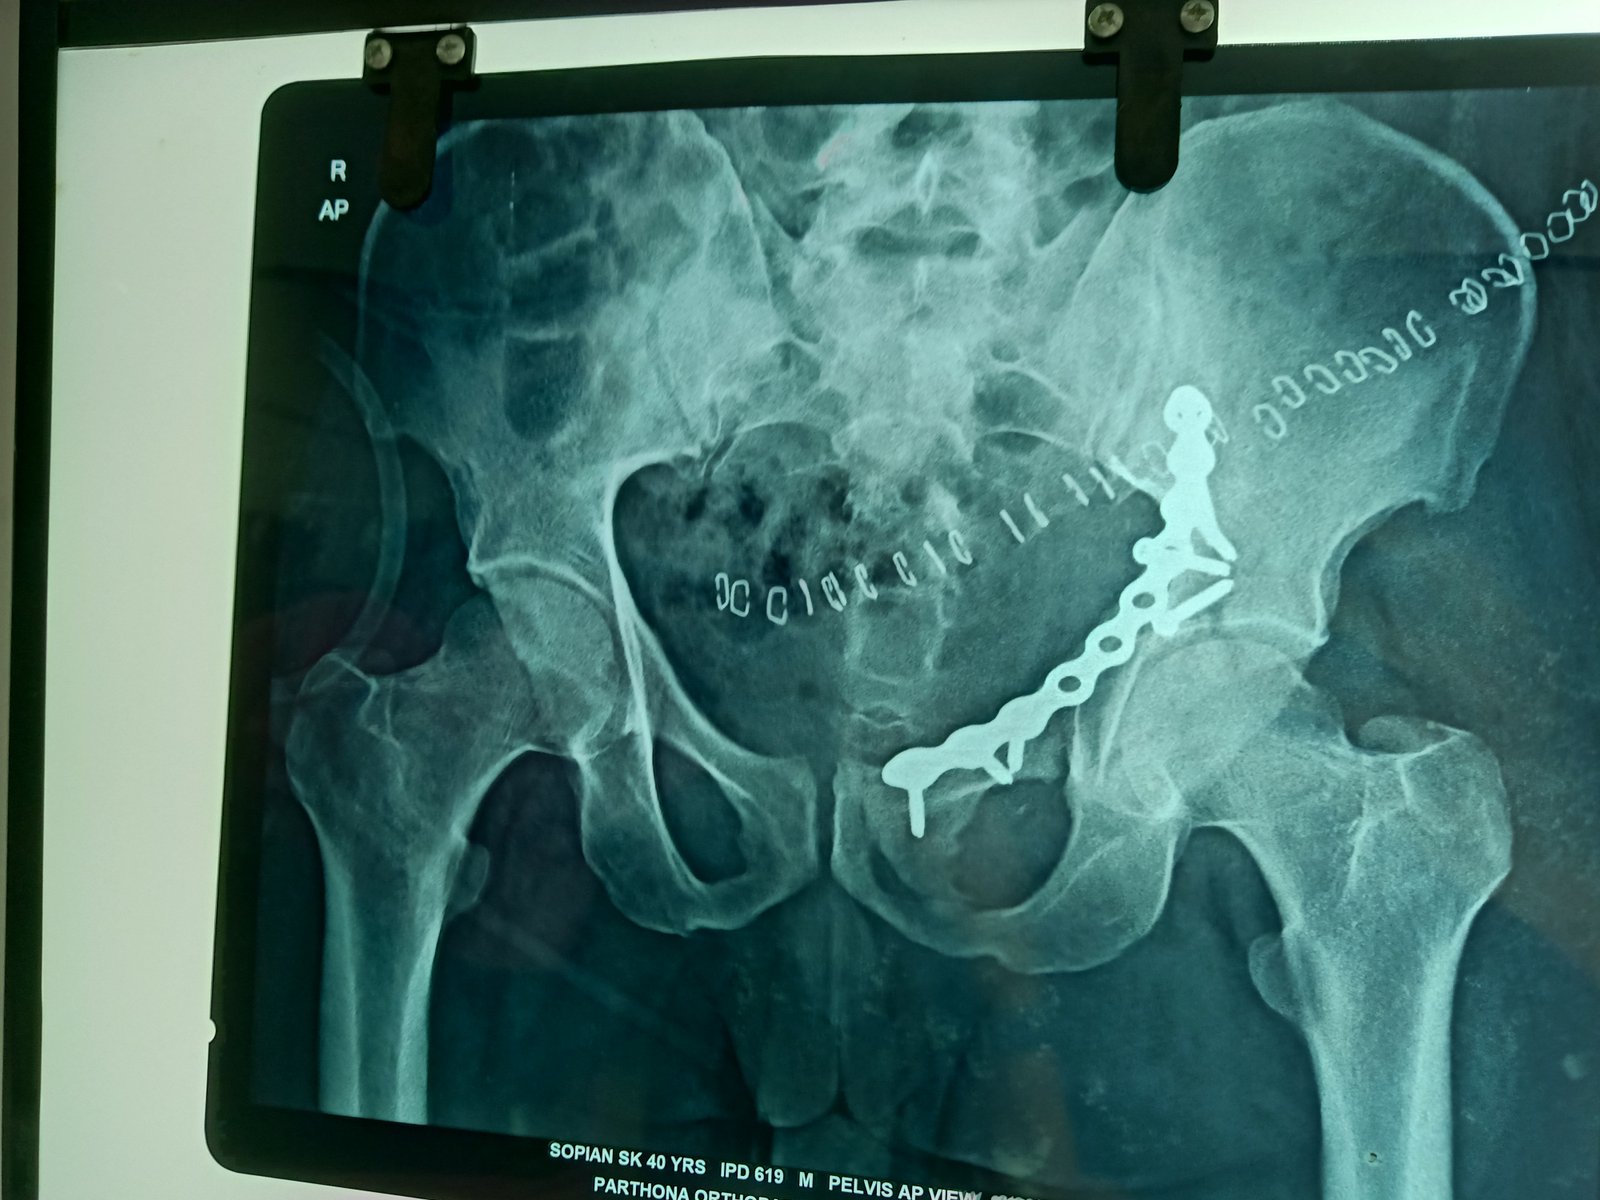

anterior collumn of acetabulum fixation done via anetrior appoach